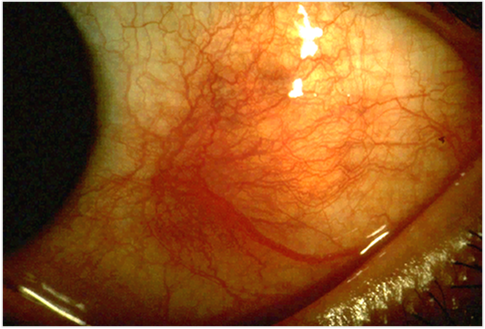

Episcleritis

Por Asagan (obra propia), CC BY-SA 3.0vía Wikimedia Commons

La epiescleritis es una enfermedad bastante frecuente. Suele aparecer rápidamente. Provoca enrojecimiento -a menudo en forma de cuña sobre la parte blanca del ojo- y molestias leves. Muchas personas pueden padecerla y no acudir nunca al médico. En ocasiones puede ser algo más dolorosa y provocar la formación de protuberancias inflamadas en la superficie del ojo. Estas protuberancias inflamadas se denominan nódulos.

Sin embargo, suele ser una afección leve sin consecuencias graves. Suele remitir por sí sola en una semana aproximadamente con un tratamiento sencillo. La epiescleritis suele ser recurrente y puede afectar a uno o ambos ojos.